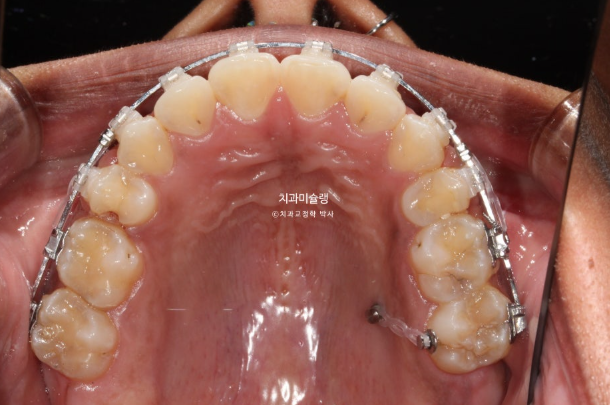

The patient opted for treatment using Clippy-C bracket orthodontics.

For effective intrusion, a temporary orthodontic mini-screw was placed in the palate.

This is the patient’s condition at 1 year and 2 months after the start of treatment.

Approximately one-third of the extraction space remains.